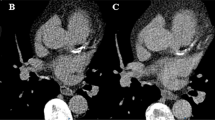

The use of TNC resulted in a mean calcium score of 178 with a minimum value of 1, a maximum value of 2048, and an inter-quartile range of 22–282. Calculations of calcium scoring using VNC spectral images of the same patients resulted in a mean calcium score of 43 with a minimum value of 0, a maximum value of 518, and an inter-quartile range of 7–56. Only one patient with a CACS of 7 on TNC images was wrongly classified as having a CACS of 0 on VNC images. Figure 1 shows a representative example of TNC, contrast-enhanced, and VNC images of a patient.